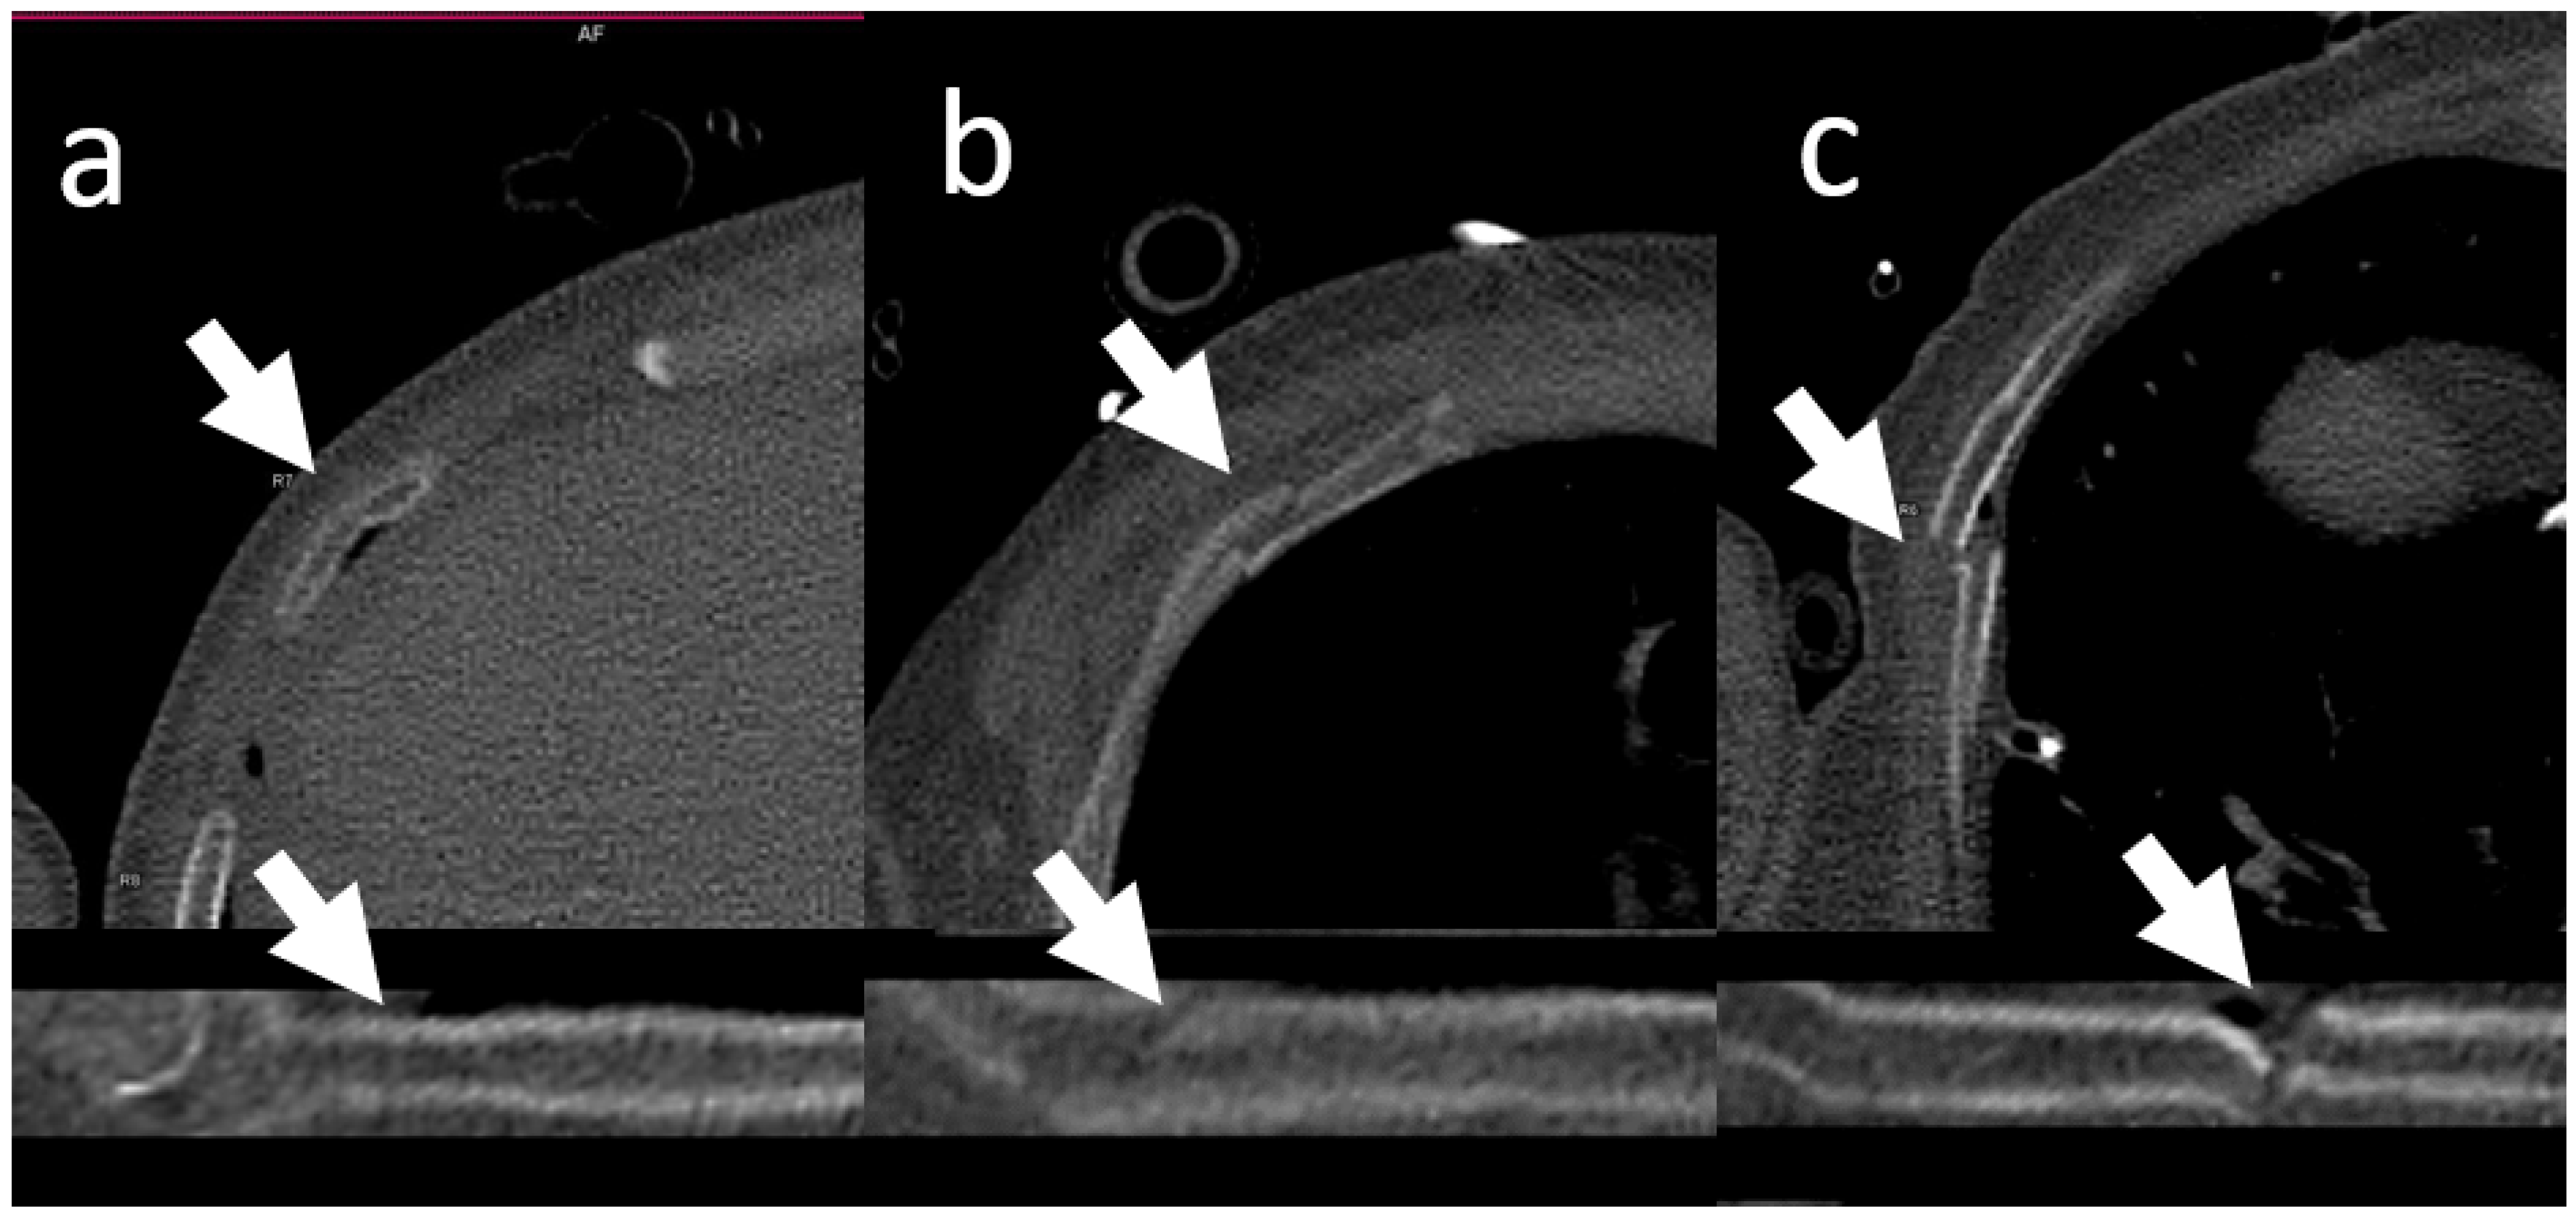

2.2. CT Acquisition and Post-Processing

2.3. Image Analysis